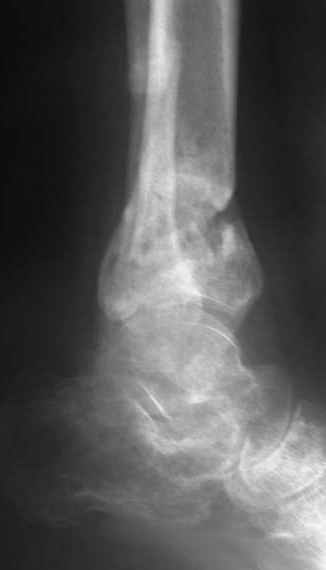

A 56 year old laborer fell off a wall approximately 5 months ago. He sustained an open pilon fracture. He was treated with debridement and external fixation. After he was treated for 4 months, the external fixator was removed.

I have attached his x-rays. I have also attached an WMV movie file of his axial CT (if you are unable to view this, I can post an MPEG file).

It seems to be a definite nonunion from the plain XRs.

The subtalar joint looks okay from what we can see on the lateral x-ray so I wouldn't want to damage it if it can be avoided. If thorough workup (WBC, ESR, CRP) shows no evidence for infection, he's a nonsmoker (or has quit) and there's no sign of infection at surgery, I would try a "moderately invasive" ORIF with debridement and autologous bone grafting. I think with a precontoured plate with locking screw capability one could get adequate fixation distally to allow immediate ROM and provide compression across the fracture.